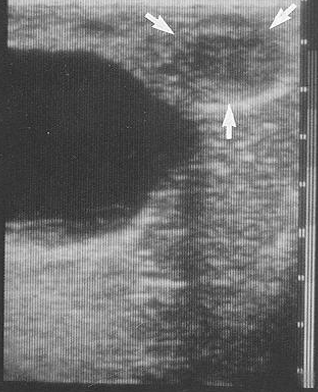

<p>Label this ultrasound of the right ovary</p>

Label this ultrasound of the right ovary

A = Ovary

B = CL

C = Follicle